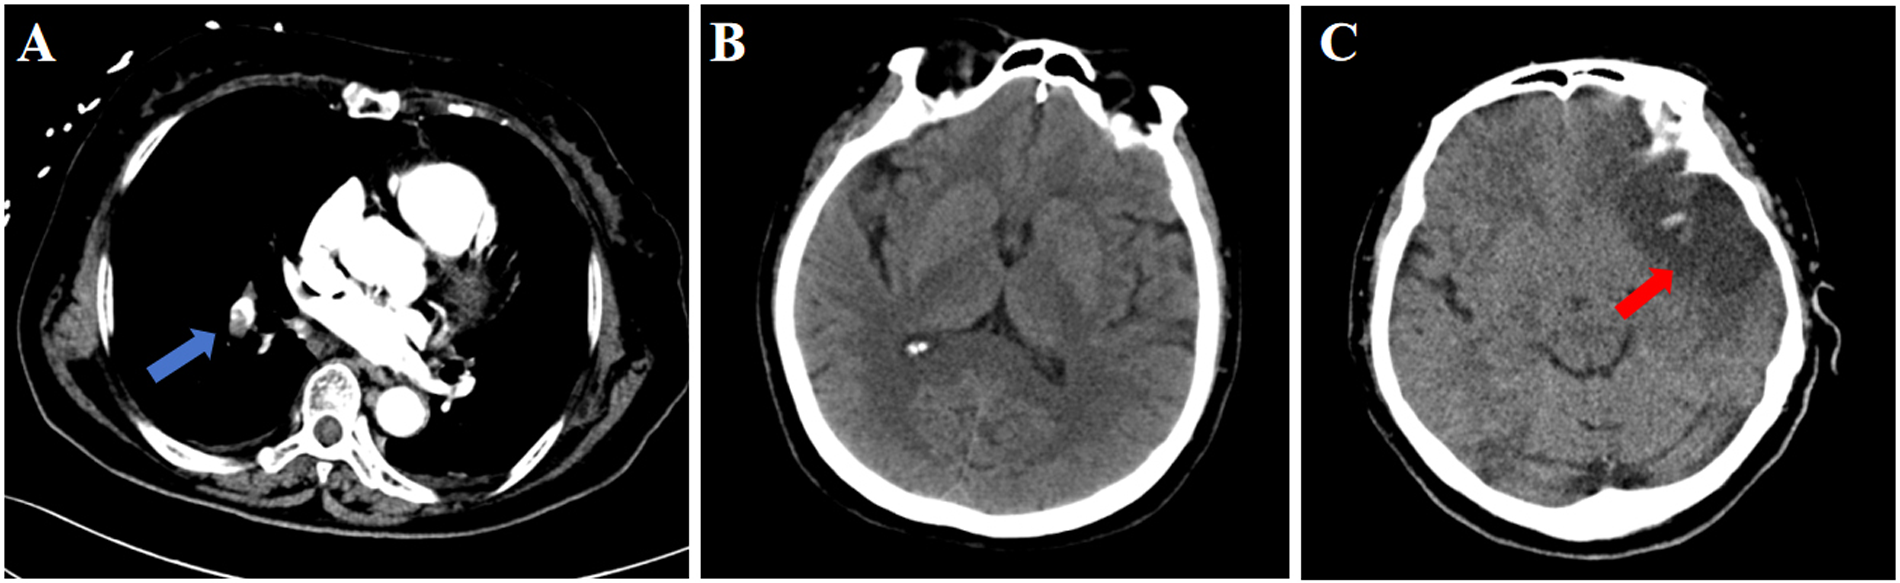

The patient underwent laparoscopic total hysterectomy with bilateral salpingo-oophorectomy under general anesthesia after admission. Intraoperative vital signs remained stable, and the procedure was completed uneventfully. On the first postoperative day, the patient experienced sudden convulsion and loss of consciousness while transitioning from a sitting to standing position, becoming unresponsive to verbal stimuli. Immediate physical examination revealed: Blood pressure 92/64 mmHg, heart rate 72 bpm, oxygen saturation 67%. Bilateral pupils were equal and round with preserved light reflex. Clear breath sounds were heard in both lung fields without rales or rhonchi. Arterial blood gas analysis revealed: pH 7.27, PO₂ 59.0 mmHg, PCO2 35 mmHg, Glucose 10.6 mmol/L, Lactate 3.5 mmol/L, Base Excess (BEb) −9.9 mmol/L. Immediate endotracheal intubation was performed with initiation of mechanical ventilation. Enhanced pulmonary CT angiography revealed pulmonary embolism (Figure 1A), while brain CT showed no significant abnormalities (Figure 1B). Transthoracic echocardiography (TTE) demonstrated trivial tricuspid regurgitation and impaired left ventricular relaxation. Lower extremity venous doppler ultrasound demonstrated partial muscular vein thrombosis in the right calf. Low molecular weight heparin calcium (0.6 ml Q12 h) was promptly initiated for anticoagulation. Subsequently, intermittent pneumatic compression (IPC) was initiated for the patient. Due to critical condition, the patient was immediately transferred to the Intensive Care Unit (ICU).

Figure 1

CT findings of the patient. (A) Pulmonary CT on postoperative day 1; (B). Cranial CT on postoperative day 1; (C). Cranial CT on postoperative day 3. Blue arrow: pulmonary embolism; Red arrow: stroke.

On postoperative day 3, early morning, the patient developed agitation and right-sided limb weakness with a positive Babinski sign on the right. Further brain CT demonstrated hypodense lesions indicating large-territory cerebral infarction in the left hemisphere (Figure 1C). Given the sequential occurrence of pulmonary embolism and cerebral infarction, the treating physicians clinically suspected a pathological right-to-left shunt pathway, such as arteriovenous fistula or PFO. TEE and bubble study was performed, revealing: Patent foramen ovale with significant right-to-left shunt (Figures 2A,B). Strongly positive bubble study (Figure 2C). The final diagnosis was PFO, pulmonary embolism and cerebral infarction.